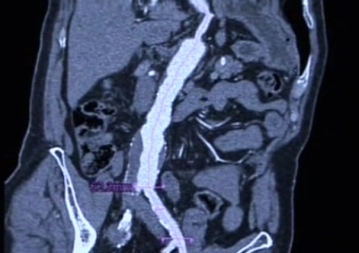

Asymptomatisch: eine rasche Größenzunahme (> 4mm pro Jahr) oder ein Querdurchmesser von > 5 cm sind klinische Entscheidungskriterien für die Operation; bei Frauen sind kleinere Durchmesser bereits rupturgefährdet.

Symptomatisch: jede Aneurysmaruptur ist eine lebensbedrohliche Situation und stellt bei allen Patienten die absolute Operationsindikation dar.

Merke: Letalität für Notfalleingriffe: > 40 %, für selektive Eingriffe: ca. 3 – 5 %